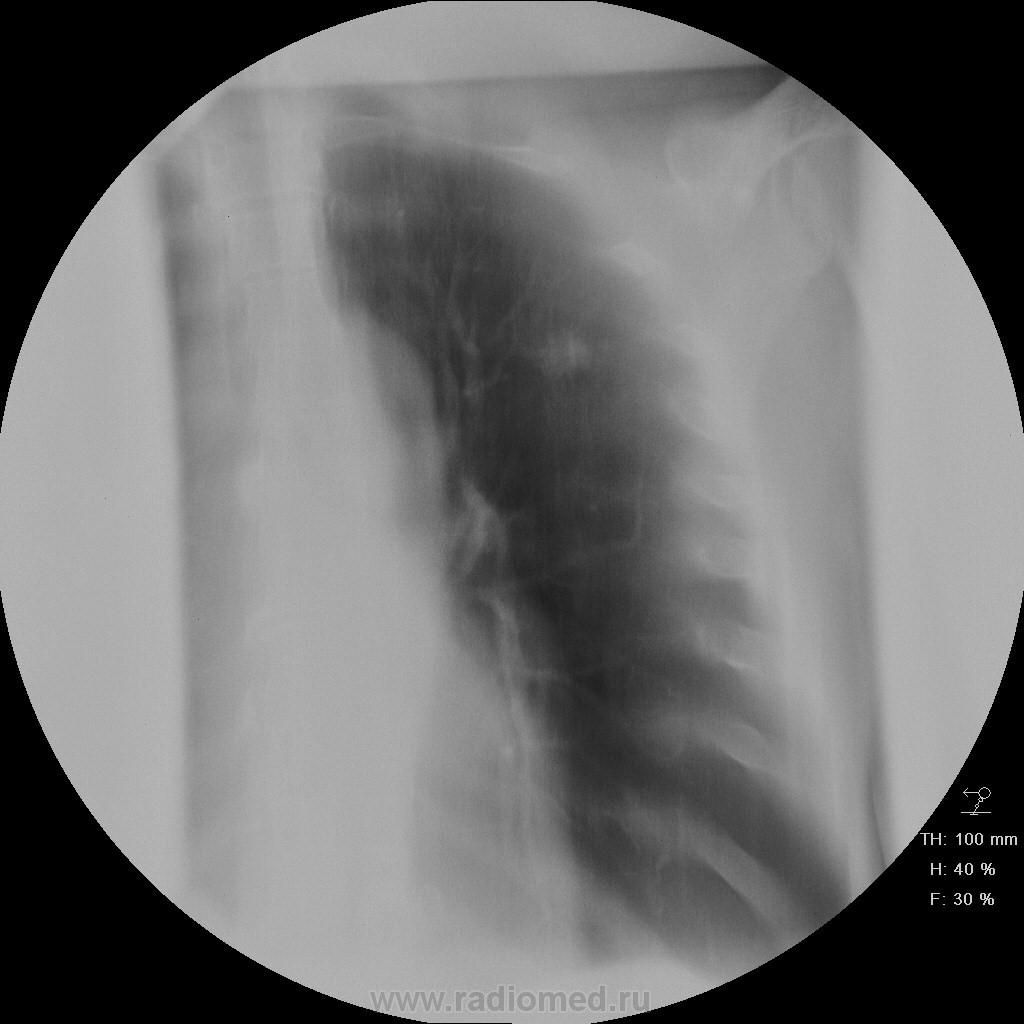

Пациет 60 лет после перенесения ОНМК. жалоб нет ( по легким) . СОЭ, лейкоциты, HB в норме.

Какие будут мнения.

КТ еще не запущен - так что выжимаем все из линейки...

Туберкулез под (?)

У больных с последствиями ОНМК следует думать об аспирационном генезе заболевания. В пользу этого свидетельствует поражение задних сегментов и двусторонняя локализация изменений.